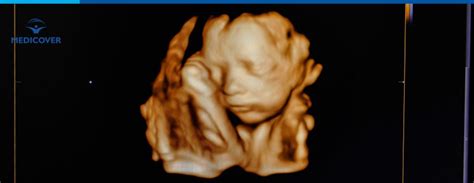

Numele de "Dublu Test" provine de la cele două investigații specifice care se realizează în cadrul acestui screening în primul trimestru, la un interval de timp de maxim 24 de ore: o ecografie morfologică fetală și o analiză de sânge pentru markeri biochimici.

- Date ecografice: vârsta biometrică, mărimea translucenței nucale (spațiul cu lichid din zona cefei fătului) și prezența osului nazal.

Dublul Test poate identifica riscul pentru:- Sindromul Down (Trisomia 21): Caracterizat frecvent prin malformații cardiace și gastrointestinale, membre scurte, clinodactilie, aplatizarea profilului și edem nucal. Pliul nucal mărit (peste 6 mm între săptămânile 11 și 14) este un marker ecografic sensibil.